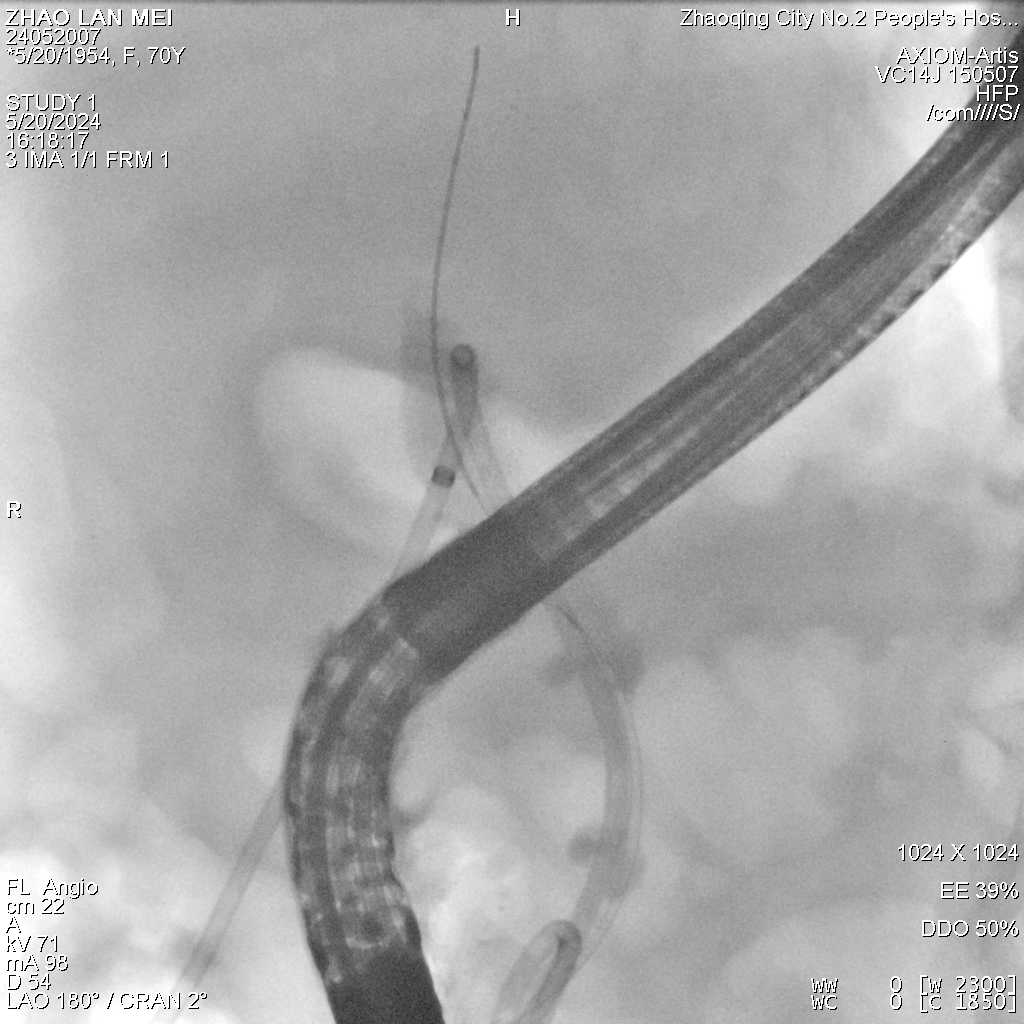

术中造影提示胆总管胰头段狭窄,胆总管乳头部正常

通过造影检查,发现胆总管下段为外压狭窄,在介入科梁威飘医师的辅助下顺利拔除PTCD引流管后,保留胆总管导丝,另一导丝顺利进入胰管,通过造影发现胰腺体部胰管狭窄,导丝不能通过也不能经副乳头出口穿出,胆总管狭窄的“元凶”终于被明确为胰头肿瘤